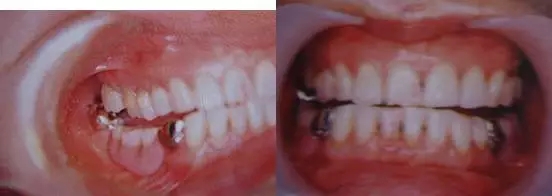

圖9. 上頜和下頜第二磨牙中發(fā)生的前方誘導(dǎo)干擾引發(fā)的張口困難。

下頜磨牙的遠(yuǎn)中頰側(cè)牙尖的近中頰側(cè)斜面和上頜磨牙的近中頰側(cè)牙尖的遠(yuǎn)中腭側(cè)斜面相接觸。

圖10. 不考慮下頜第三磨牙的咬合平面破壞的修復(fù)體制作完成后,后方磨牙干擾引發(fā)的前方誘導(dǎo)干擾。